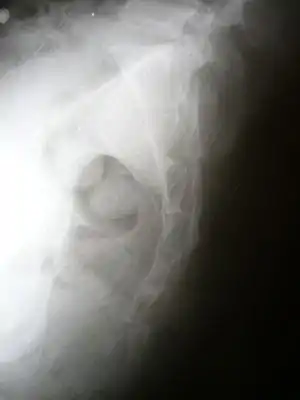

Lateral radiograph showing a fracture of the coccyx, as well as a lower lumbar fracture